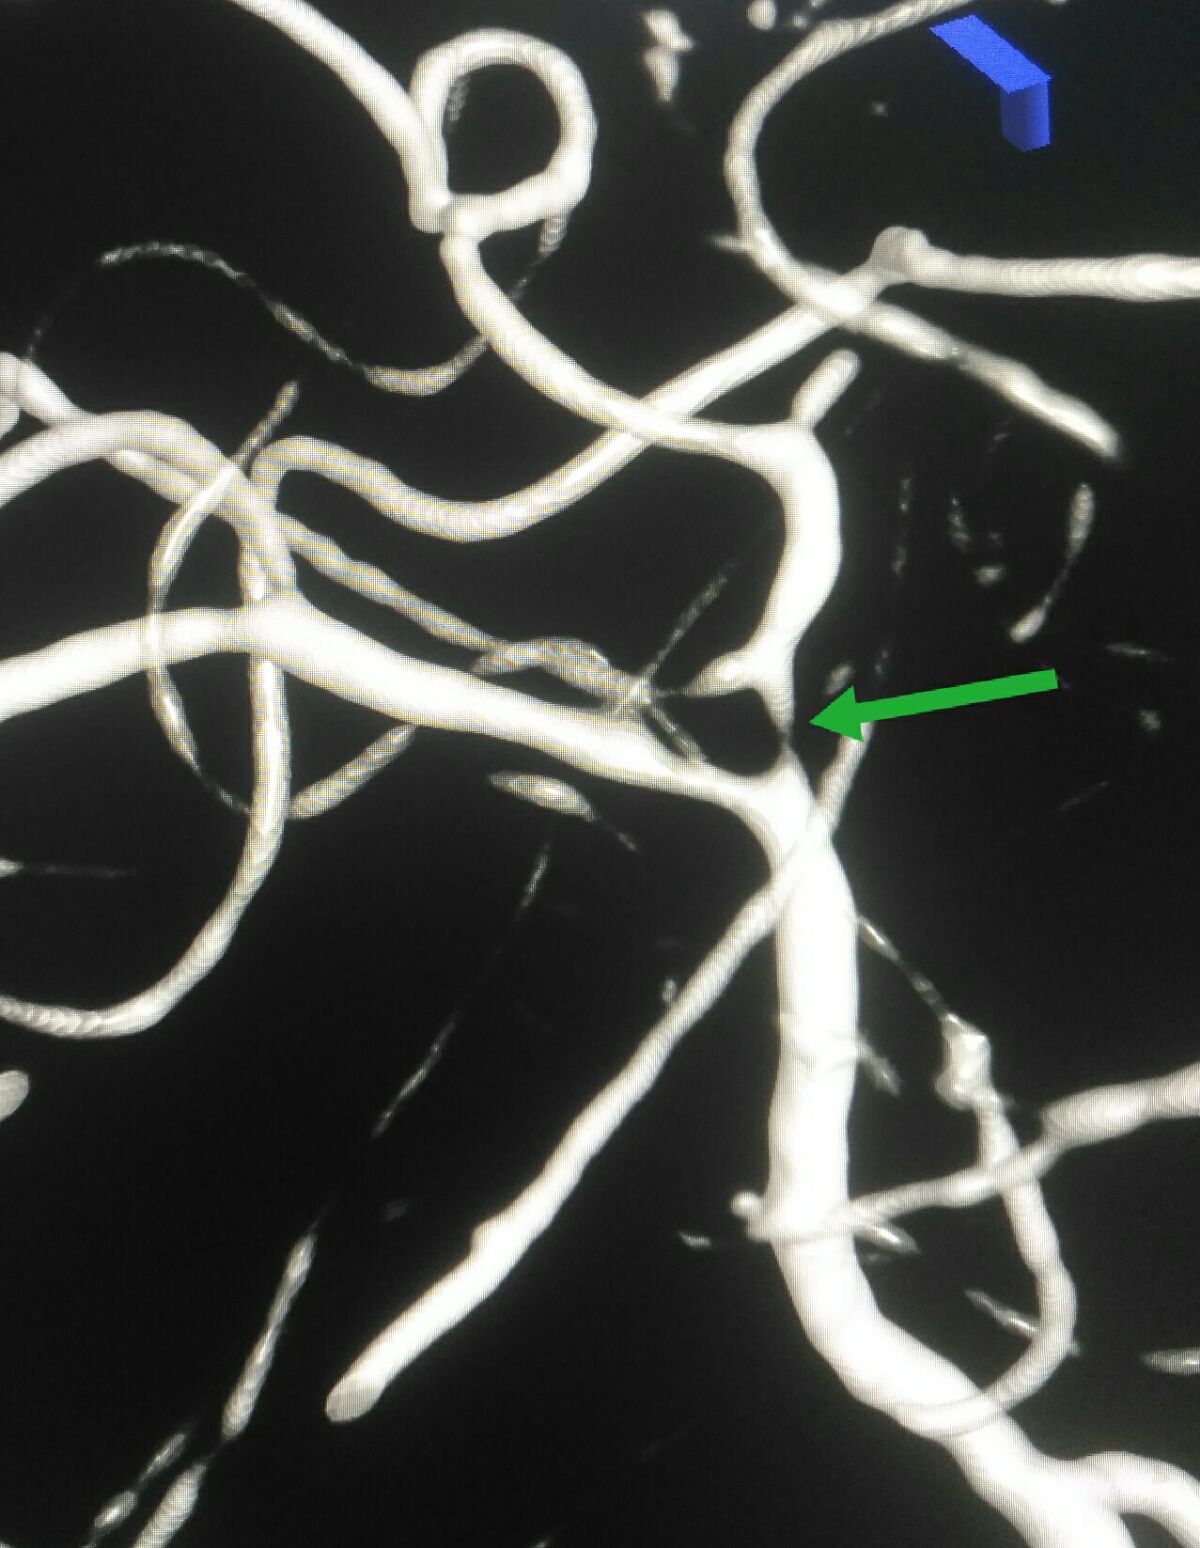

3D处理后可见大脑中动脉下干重度狭窄

3D处理后可见大脑中动脉下干重度狭窄

3D处理后不同角度显示大脑中动脉下干重度狭窄